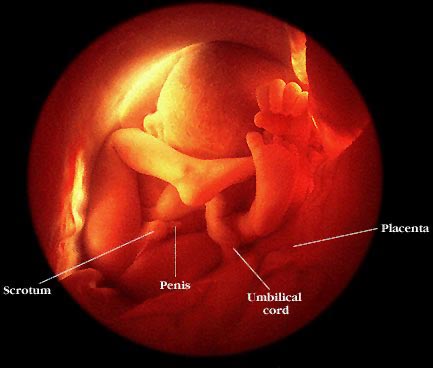

Veled mi újság? Gyerkőcök jól vannak? Kapaszkodnak erősen? Jajj csajszi, belegondoltál, hogy mi lesz, ha ikreket szülsz??? Egyik ismerősömék akartak másodikat és hármas ikrek lettek... elég húzós, már most fáj a fejük mi lesz, ha négy gyerek lesz. Nem lombik, spontán terhességből vannak a bébik. Azért nem semmi. Nagyon drukkolok Nektek továbbra is, hogy minden simán menjen!